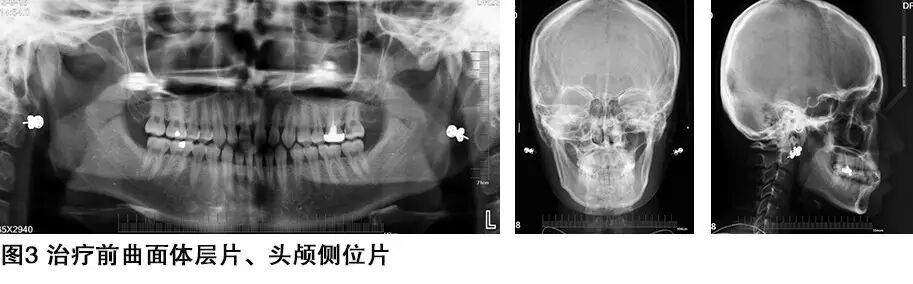

检查:恒牙列,双侧磨牙基本中性关系,中线基本对称。前牙13、12、11、21、22、23、31、32、33、41、42、43 有 间隙,反合。26原治疗齿烤瓷冠修复,16 、36 原银汞充填齿,37、47 窝沟龋,直面型,颜面发育不对称,眼平面偏斜,开口型正常,双侧关节无弹响,从侧貌看患者有轻微的上唇发育不足,上前牙发育过小,Bolton指数不调。牙周检查:全口口腔卫生良好,无软垢,牙龈颜色 形态 质地正常,BOP(一),牙石0度,全口牙周健康,无松动牙。

诊断:安氏Ⅰ,毛氏Ⅰ类二分类,前牙反合。

1、根据头影测量结果显示,患者反合不属于骨性畸形,属于牙性畸形,所以先进行牙齿矫正,解决前牙反合,关闭散在的间隙,由于Bolton指数不调,可能存在有的间隙不能完全的关闭。